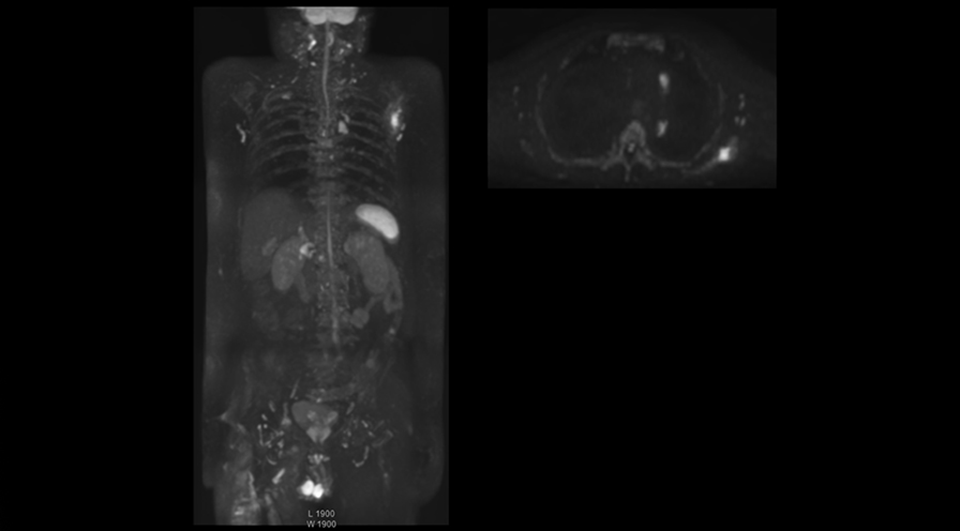

Radiologist Hiroshi Nobusawa, MD, PhD, explains that the coronal DWIBS protocol for whole body DWI is excellent for visualizing lesions in oncology patients. “About 90% of the DWIBS exams are done in this type of patients. The remainder of DWIBS exams are performed to gain information in cases of fevers of unknown origin,” he says. in image acquisition and postprocessing algorithms.”“mDIXON TSE sequences allow simultaneous characterization of morphological changes from the in-phase T2-weighted images and visualization of edematous changes, thanks to the water T2-weighted images from the same acquisition. Anatomical and morphological considerations could be a partial or complete ligament tear, a bony avulsion or hematoma.” “For soft tissue assessment mDIXON brings similar benefits. For example in one T2-weighted mDIXON TSE acquisition, having the multiple contrasts helps us assess abnormalities in peripheral nerves fascicles, which may be due to anatomical or inflammatory changes..” “In peripheral joints, we get good image quality in difficult areas with mDIXON TSE. Fat suppressed images appear homogeneous over the entire image, even with large coverage at 3.0T – for instance in scapular or hip girdles – or in the bearing areas or around metal prostheses*, where fat suppression is often deficient with STIR or spectral fat suppression, causing diagnostic difficulties. If a diagnostic image is right the first time, we don’t need to repeat or add a sequence.” “mDIXON TSE sequences allow simultaneous characterization of morphological changes from the in-phase T2-weighted images and visualization of edematous changes, thanks to the water T2-weighted images from the same acquisition. Anatomical and morphological considerations could be a partial or complete ligament tear, a bony avulsion or hematoma.” “For soft tissue assessment mDIXON brings similar benefits. For example in one T2-weighted mDIXON TSE acquisition, having the multiple contrasts helps us assess abnormalities in peripheral nerves fascicles, which may be due to anatomical or inflammatory changes..”

“The DWIBS sequence’s value in oncology cases is due to the high contrast it creates between lesions and surrounding tissue. Whole body DWI is requested by physicians who need to clarify TNM staging or determine therapeutic strategies, oncologists in need of diagnosis or follow-up scans, surgeons who need to see the presence of distant lesions that are sometimes difficult to detect by CT before surgery, and urologists for the evaluation of bone lesions, and the effect of chemotherapy and radiotherapy.”

“Switching to coronal DWIBS – rather than axial – further shortens scan time,” says Mr. Naka. “Important is that a dS SENSE factor of 5 shortens exam time while high image quality can be maintained, thanks to Ingenia’s dStream architecture.” He adds that the coronal orientation also avoids artifacts that are specific to combining axial images.

“When we use a coronal DWIBS acquisition, we can perform a full whole body examination, including other required sequences, within 30 minutes,” he says.

Dr. Nobusawa notes that acceptance of whole body DWI accelerated after the hospital installed the Ingenia 1.5T which allowed them to optimize the protocol to their needs. “The Philips system helped us promote the technique, because the DWIBS image quality was so high with Ingenia. It provides high quality in the coronal images, and a short acquisition time plus high SNR thanks to the dStream technology,” he says.